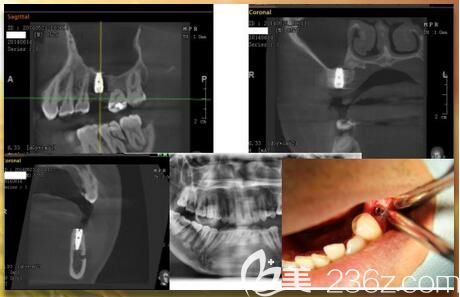

1、種植前充分做好CT分析,可以有效的檢查出顧客種植牙區(qū)域的狀況,使植牙的手術(shù)過(guò)程中更安全。

2、運(yùn)用3D數(shù)字導(dǎo)板技術(shù),有效的量身制定專屬的種植牙方案。

3、采用數(shù)字化微創(chuàng)種植手術(shù),使創(chuàng)傷小、出血量少、成活率高、恢復(fù)、種植體更穩(wěn)固。